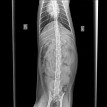

Рентген (без контраста) – показал что все в норме (со слов врача) ренген прикреплен ниже. Заключение по рентгену мне не выписывали, только снимок.

Рентген и назначение от 28.01.19